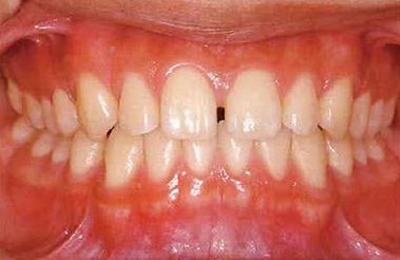

患牙齦炎的牙周組織的臨床圖像

22歲男性牙齦炎的臨床圖像

22歲男性,抽煙(1天約15根,煙齡5年)。刷牙狀態(tài)不佳。抽煙者特有的纖維性牙齦,未見發(fā)紅、腫脹。探針觸診,所有部位均出血。X線牙片未見骨吸收,診斷為牙齦炎。

14歲男性牙齦炎的臨床圖像

14歲男性。刷牙狀態(tài)不佳。整顎浮腫性發(fā)紅、腫脹且刺激出血。牙頸部有早期齲(白斑)。

26歲男性牙齦炎的臨床圖像

26歲男性。開口呼吸?;旌嫌醒例l發(fā)紅、腫脹與纖維性肥厚。菌斑干燥牢牢黏住,刷牙難以刷掉。